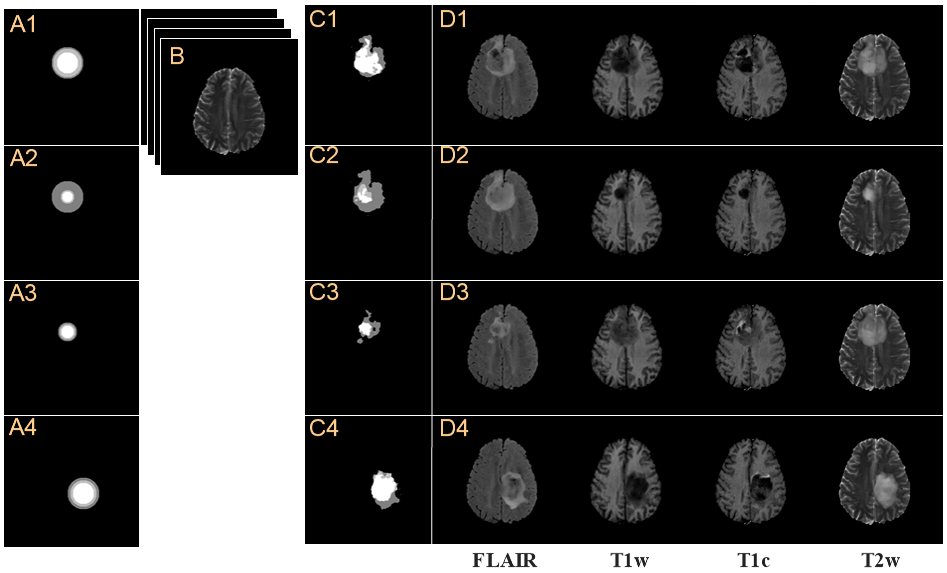

Refer to caption

Figure 5: Synthesized brain tumor images, X^Tsubscript^X𝑇\hat{\textbf{X}}_{T}, from various concentric circles, c𝑐c, with a given normal brain image, XNsubscriptX𝑁\textbf{X}_{N}. (A1-A4) Various concentric circles and (B) the given multi-contrast normal brain image, XNsubscriptX𝑁\textbf{X}_{N}. (C1-C4) Grade tumor masks, m^gradesubscript^𝑚𝑔𝑟𝑎𝑑𝑒\hat{m}_{grade}, generated from various concentric circles. (D) Synthesized multi-contrast brain tumor images, X^Tsubscript^X𝑇\hat{\textbf{X}}_{T}.

We analyzed how the synthesized image changes depending on the size and position of the concentric circles with a given XNsubscriptX𝑁\textbf{X}_{N} as shown in Fig.5. The grade tumor masks are generated by Ggradesubscript𝐺𝑔𝑟𝑎𝑑𝑒G_{grade} as shown in Fig.5(C1-C4), generated with the given XNsubscriptX𝑁\textbf{X}_{N} in Fig.5(B) and various concentric circles in Fig.5(A1-A4). The m^gradesubscript^𝑚𝑔𝑟𝑎𝑑𝑒\hat{m}_{grade} are generated according to the sizes, locations, and grade information of the concentric circles. In the cases of Fig.5(A1) and (A2) having the same size and position but different grade information, the generated tumor masks in Fig.5(C1) and (C2) have the same appearance, but only different grade information of m^gradesubscript^𝑚𝑔𝑟𝑎𝑑𝑒\hat{m}_{grade}. In the cases of Fig.5(A1) and (A3) having the same location but different sizes and grade information, m^gradesubscript^𝑚𝑔𝑟𝑎𝑑𝑒\hat{m}_{grade} in Fig.5(C1) and (C3) are in the same location, but have different appearances and grade information. The concentric circles in Fig.5(A1) and (A4) have the same size and same grade information, but different locations. The m^gradesubscript^𝑚𝑔𝑟𝑎𝑑𝑒\hat{m}_{grade} in Fig.5(C1) and (C4) have the same size and grade information, but are different in appearance. These results show that the appearance of the tumor mask is affected by the size, grade information and location of the concentric circles. The images, X^Tsubscript^X𝑇\hat{\textbf{X}}_{T}, in Fig.5(D1-D4) were synthesized through Fig.5(A1-A4) and (B). The tumor parts of the synthesized brain tumor images depend on the concentric circles. It is proven that even one XNsubscriptX𝑁\textbf{X}_{N} can be used to synthesize a variety of X^Tsubscript^X𝑇\hat{\textbf{X}}_{T} if various concentric circles are used.